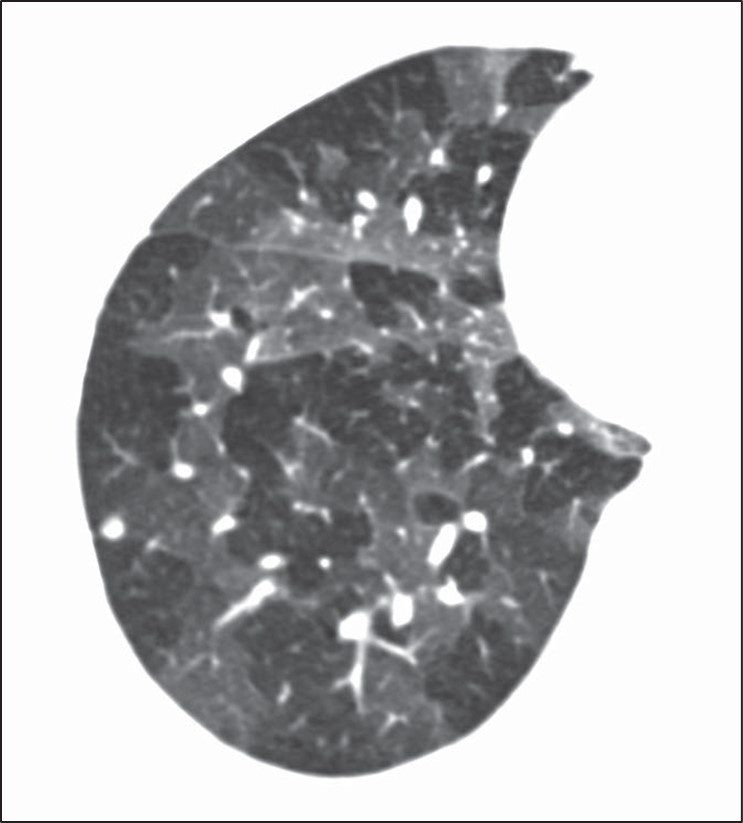

Although many centrilobular nodules may be present in lymphatic diseases, nodules should also be seen in the peribronchovascular or sub- pleural interstitium. This is in distinction to the centrilobular pattern in which only centrilobular nodules are present and no subpleural nodules should be seen. Lastly, diseases typically associated with a perilymphatic distribution of nodules (such as sarcoidosis) may occasionally show a fairly homogeneous involvement of the lung, mimicking a random distribution [27] (Fig. 11).

Fig. 11—Axial high-resolution CT scan shows perilymphatic distribution mimicking random nodules. Innumerable tiny nodules are present. Although pattern resembles random distribution, heterogeneous distribution in lung shows proportionally more nodules along fissures (arrows) than would be expected for random distribution.

A greater number of nodules in the subpleural or peribronchovascular interstitium may be the only clue that the distribution is perilymphatic.